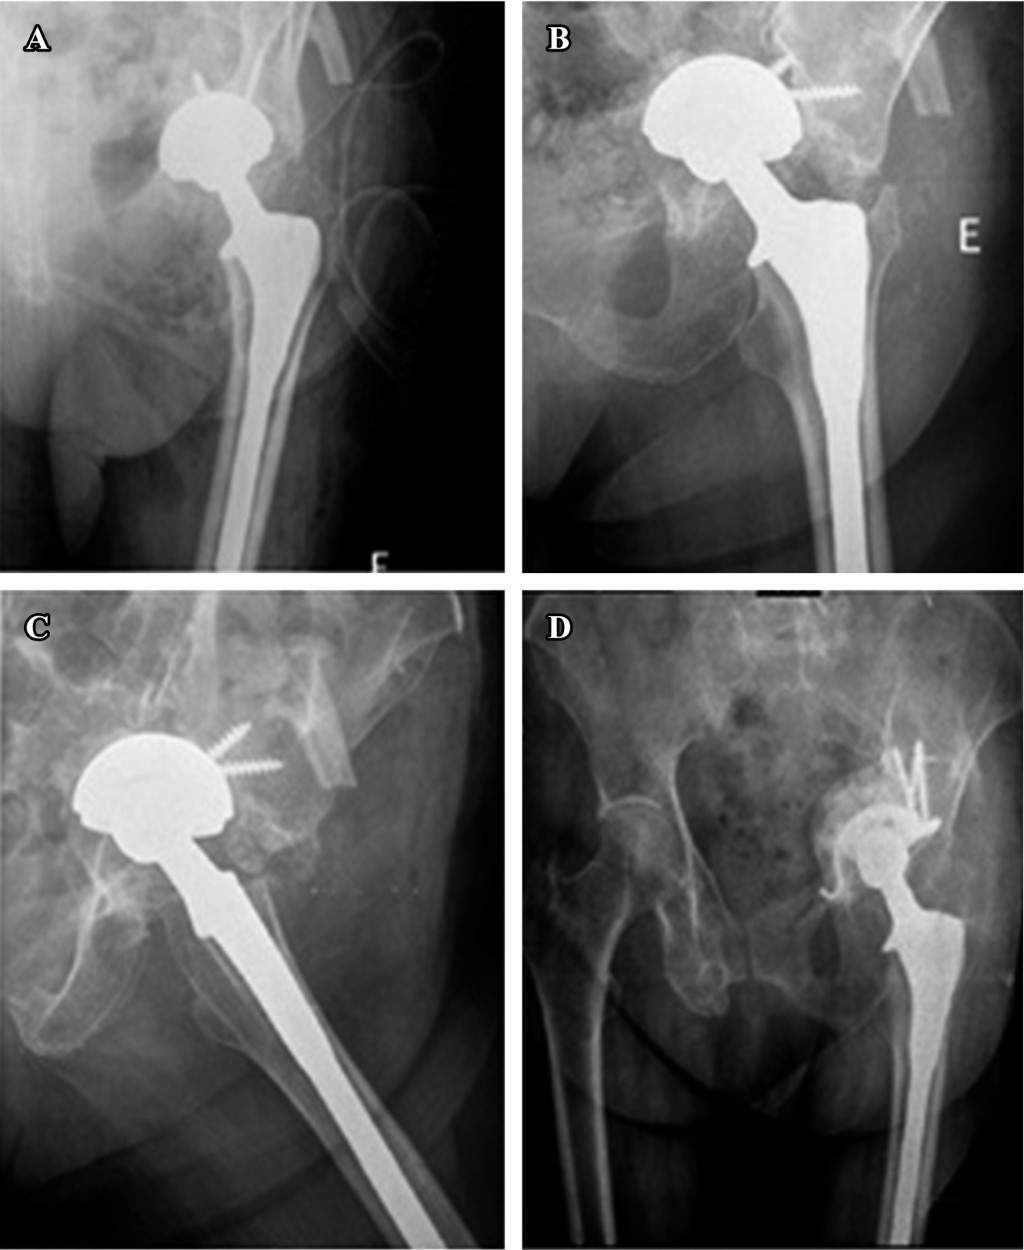

También se puede asociar con fracturas acetabulares. Ocurre debido al bloqueo del suministro de sangre a la cabeza femoral (bola) por daño arterial que conduce a la necrosis de la cabeza del fémur. Prevención. Puede prevenir las fracturas acetabulares al: Usar cinturones de seguridad y conducir con seguridad.. An updated bibliographic review on the classification of acetabulum fractures was made. There were analysed important aspects of the international classification that divides these fractures into partially articular, with affection of one or both columns, and complex articular that specify all the variants in every case.